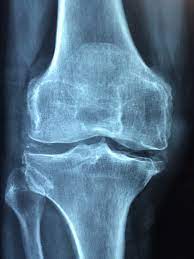

관절은 뼈와 뼈 사이가 부드럽게 운동할 수 있도록

연골, 관절낭, 활막, 인대, 힘줄,

근육 등으로 구성되어 있으며,

움직임에 따라 발생하는 충격을 흡수하는 역할을 합니다.

뼈의 상단부위는 연골로 되어 있고

연골은 혈관이 없이 관절액에서 영양을 흡수합니다.